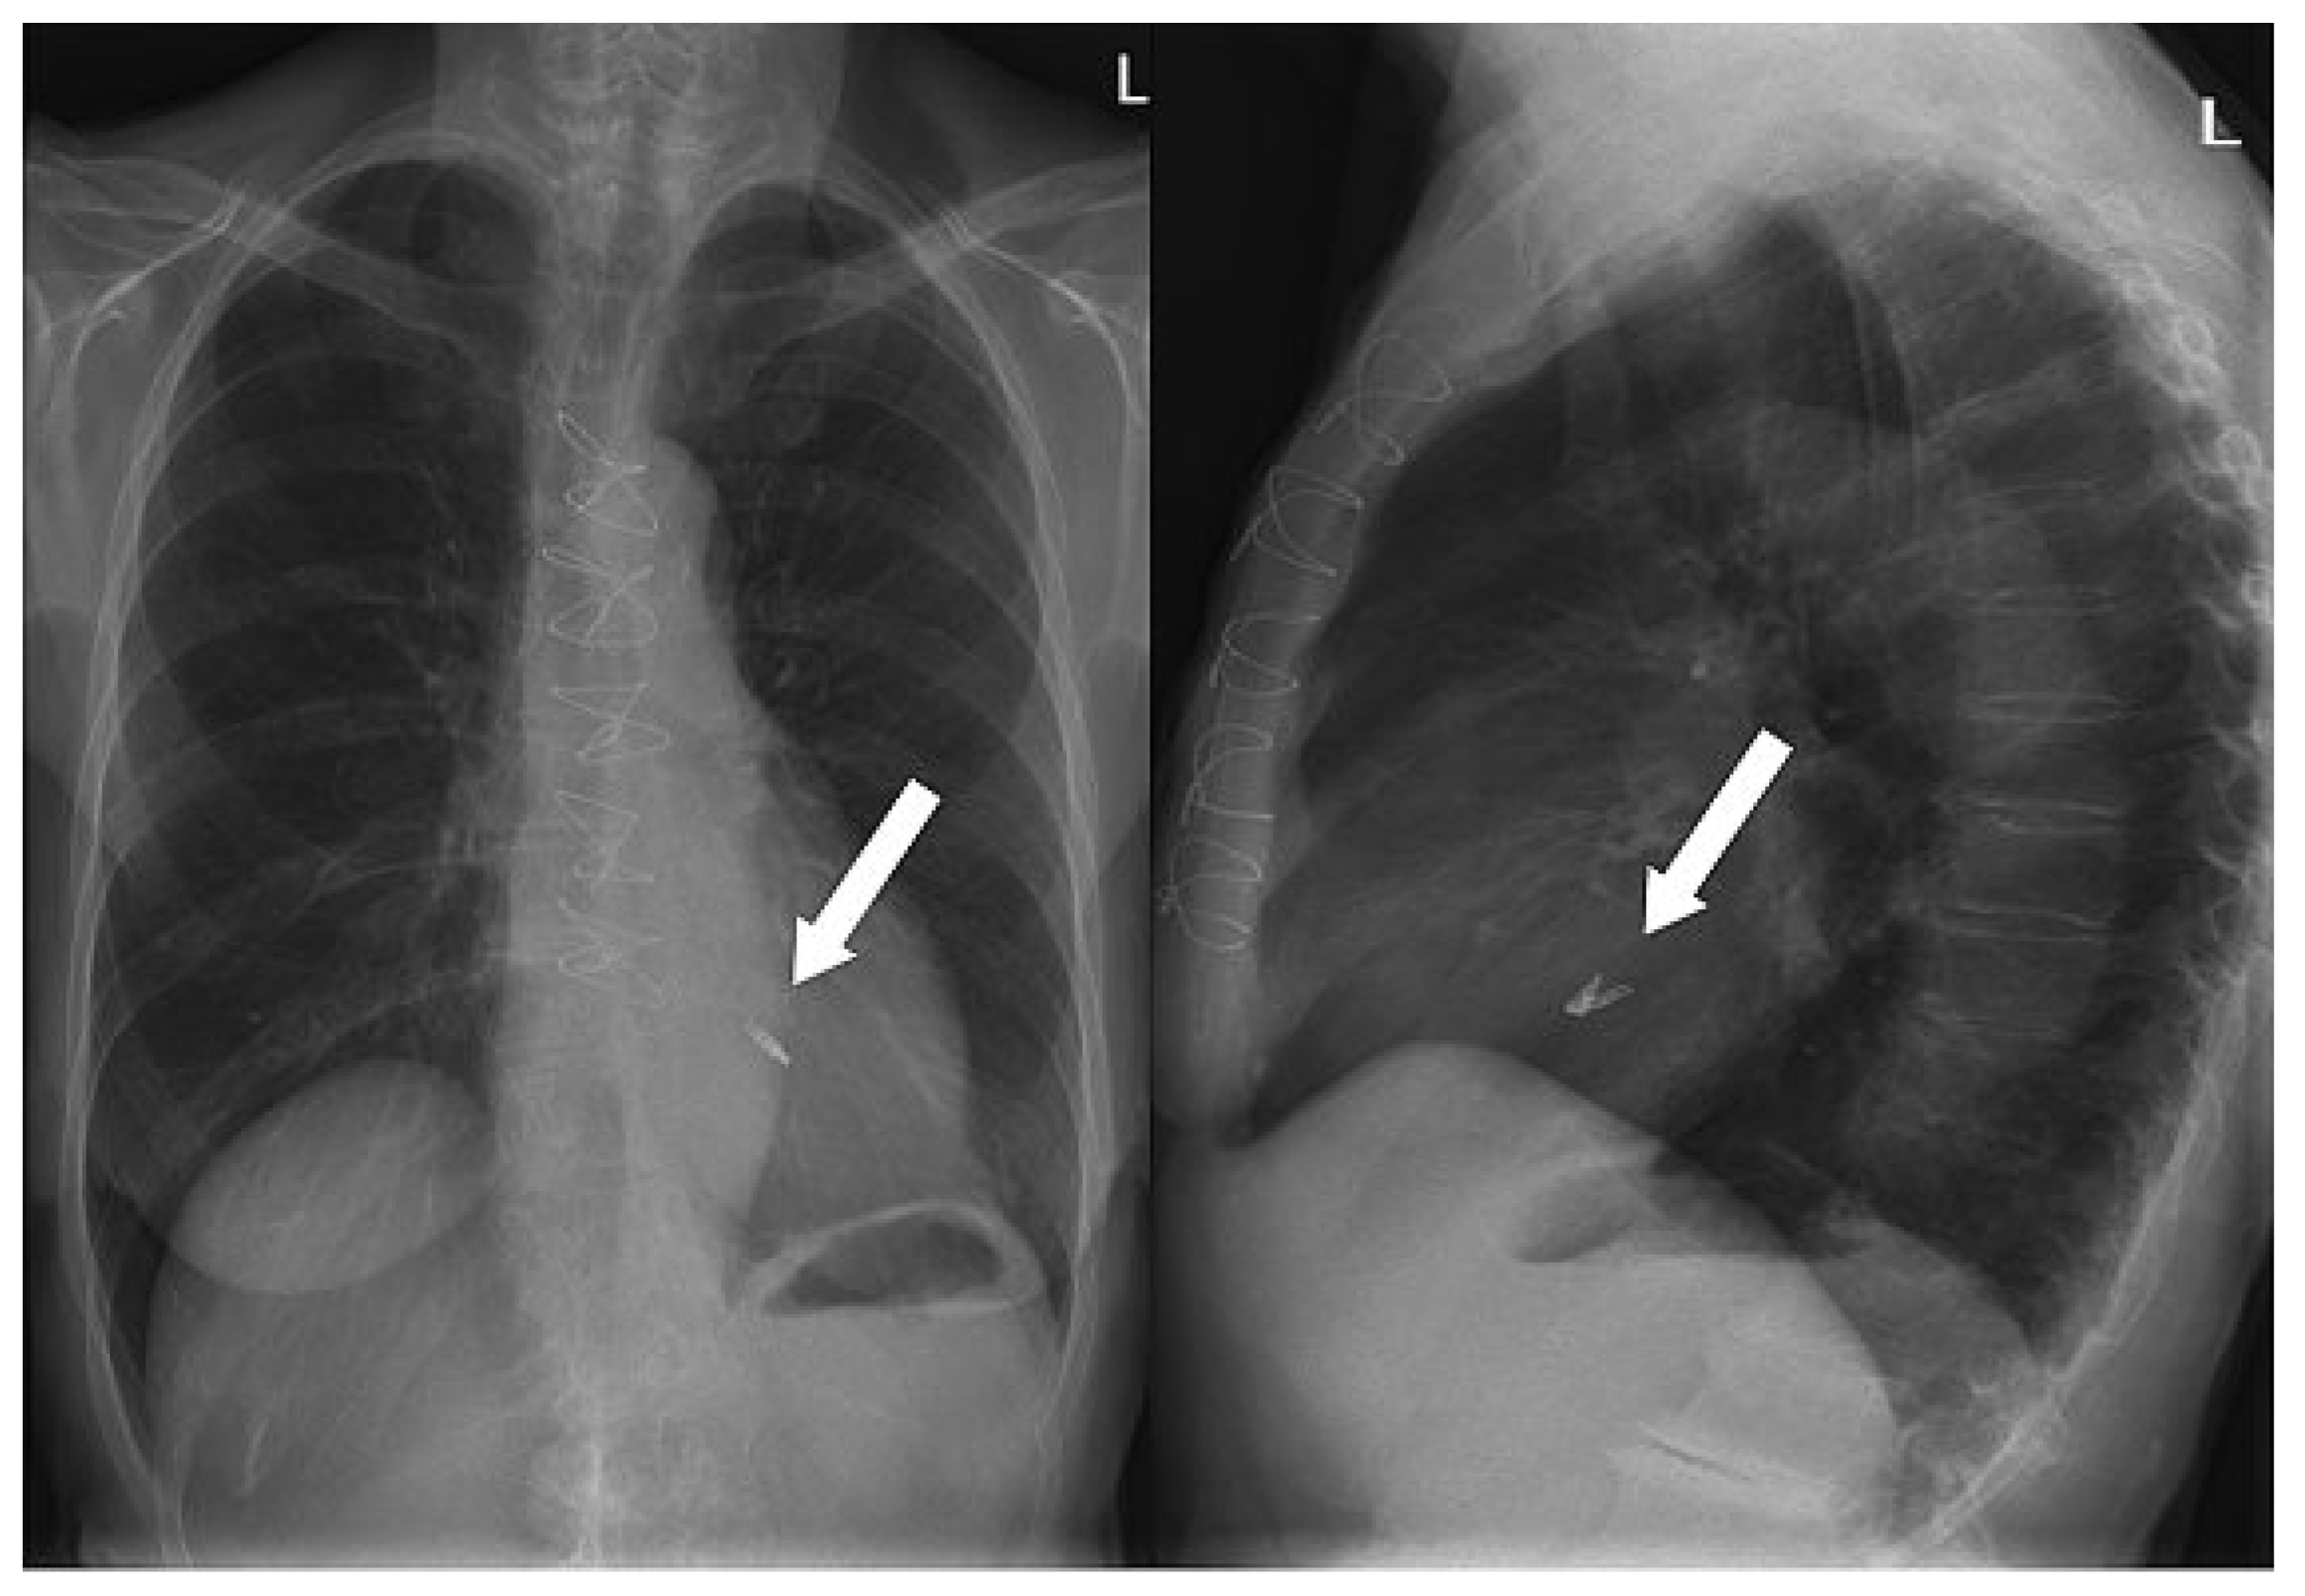

After gaining access through an 8 french sheath via the right femoral vein, transseptal puncture was performed under TEE and fluoroscopic-guidance, and an Amplatz-Super-Stiff® catheter was advanced into the left atrium (fig. 3A–C). Changing to a MitraClip-guide catheter, the clip delivery system was advanced via the left atrium (fig. 3D) into mitral position (fig. 3E). The system allows repositioning of the device under echocardiographic control until optimal placement has been found. This meant, before releasing the Clip (fig. 3F), that it could be repositioned until echocardiographic control showed the correct position of the device with mild residual regurgitation (fig. 4). 3-dimensional echocardiographic reconstruction images allowed the positioning and adjusting of the clip (fig. 5A) and the open and closed mitral valve after MitraClip® placement (fig. 5B and 5C) to be seen. The patient could be extubated in the catheter lab directly after clip implantation. The in-hospital recovery was uneventful and the patient could be discharged home three days after the intervention. During her four-week follow-up, the patient was in excellent health and reported a substantial improvement of her symptoms, reducing her exertional dyspnoea symptoms down to NYHA I–II. Echocardiographic control showed the MitraClip® in an optimal place with a residual mild-moderate regurgitation jet. On the chest x-ray film, the metallic clip can easily be identified (fig. 6).

Figure 6. Chest x-ray showing the position of the MitraClip®.